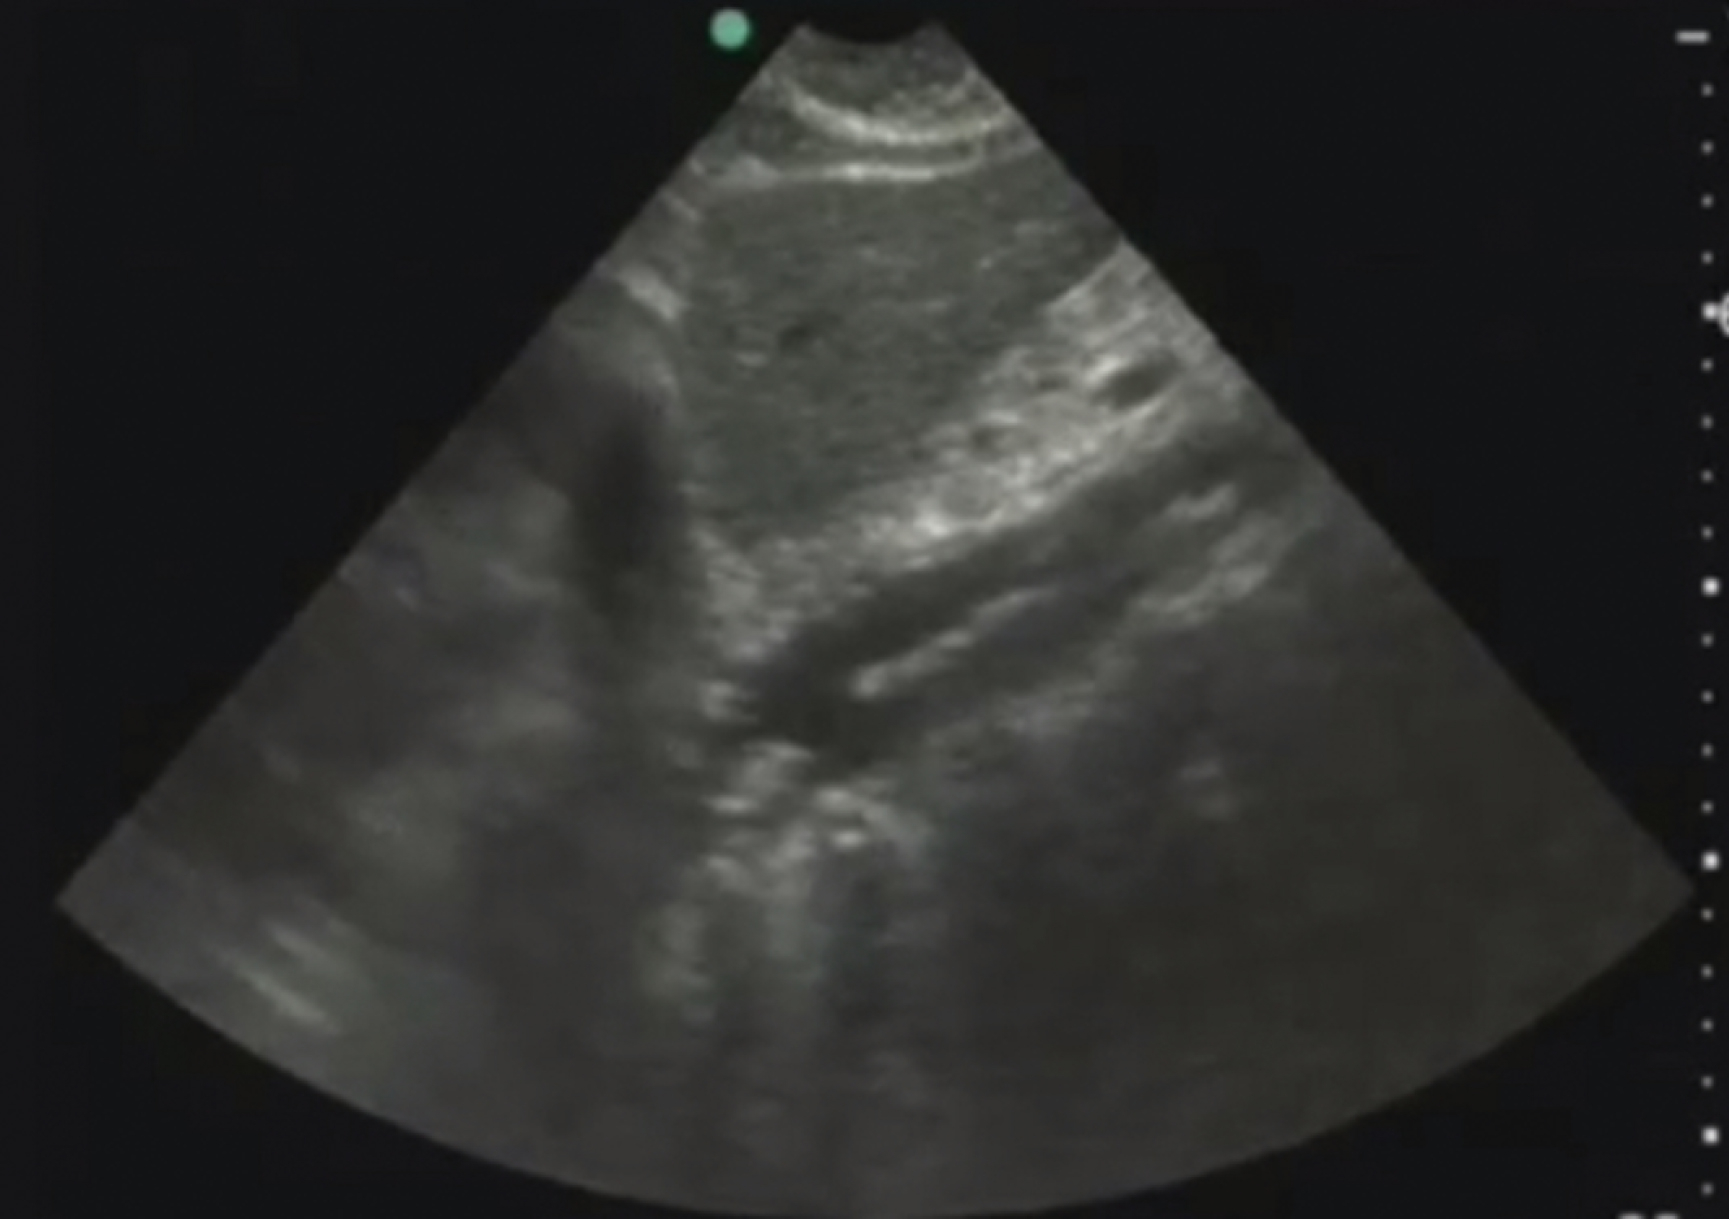

Pathology

Hydronephrosis is characterized by dilation and anechoic fluid accumulation within the renal pelvis and calyces, ranging from mild to severe ( Fig. e3.6 ). Renal and/or ureteral calculi may be identified as echogenic foci with associated shadowing and are usually located within the kidney (nonobstructive) or in the renal pelvis, proximal ureter, or uretero-vesicular junction. Color Doppler placed over the kidney can help differentiate mild hydronephrosis from the renal vasculature, as well as possibly accentuate any renal stones by producing the renal twinkle artifact.

Fig. e3.6

Hydronephrosis with dilation of the calyces and renal pelvis of the kidney showing thinning of the cortex, signifying severe hydronephrosis.